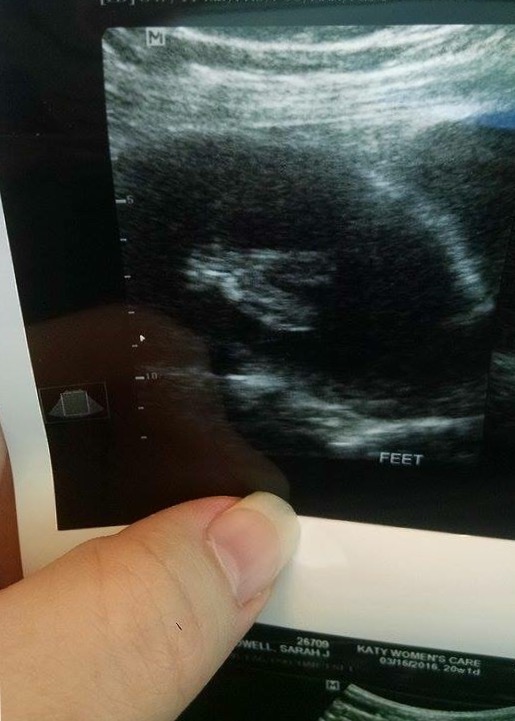

The tech that I paid said it was actually going to be a dolphin but I figured y'all knew more than her.